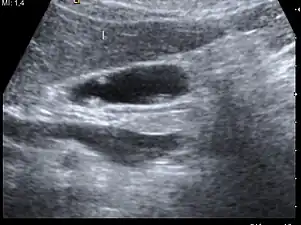

Ultrasound image of gallbladder polyps measuring 3–7 mm.

Diagnosis is typically by ultrasound or CT imaging.